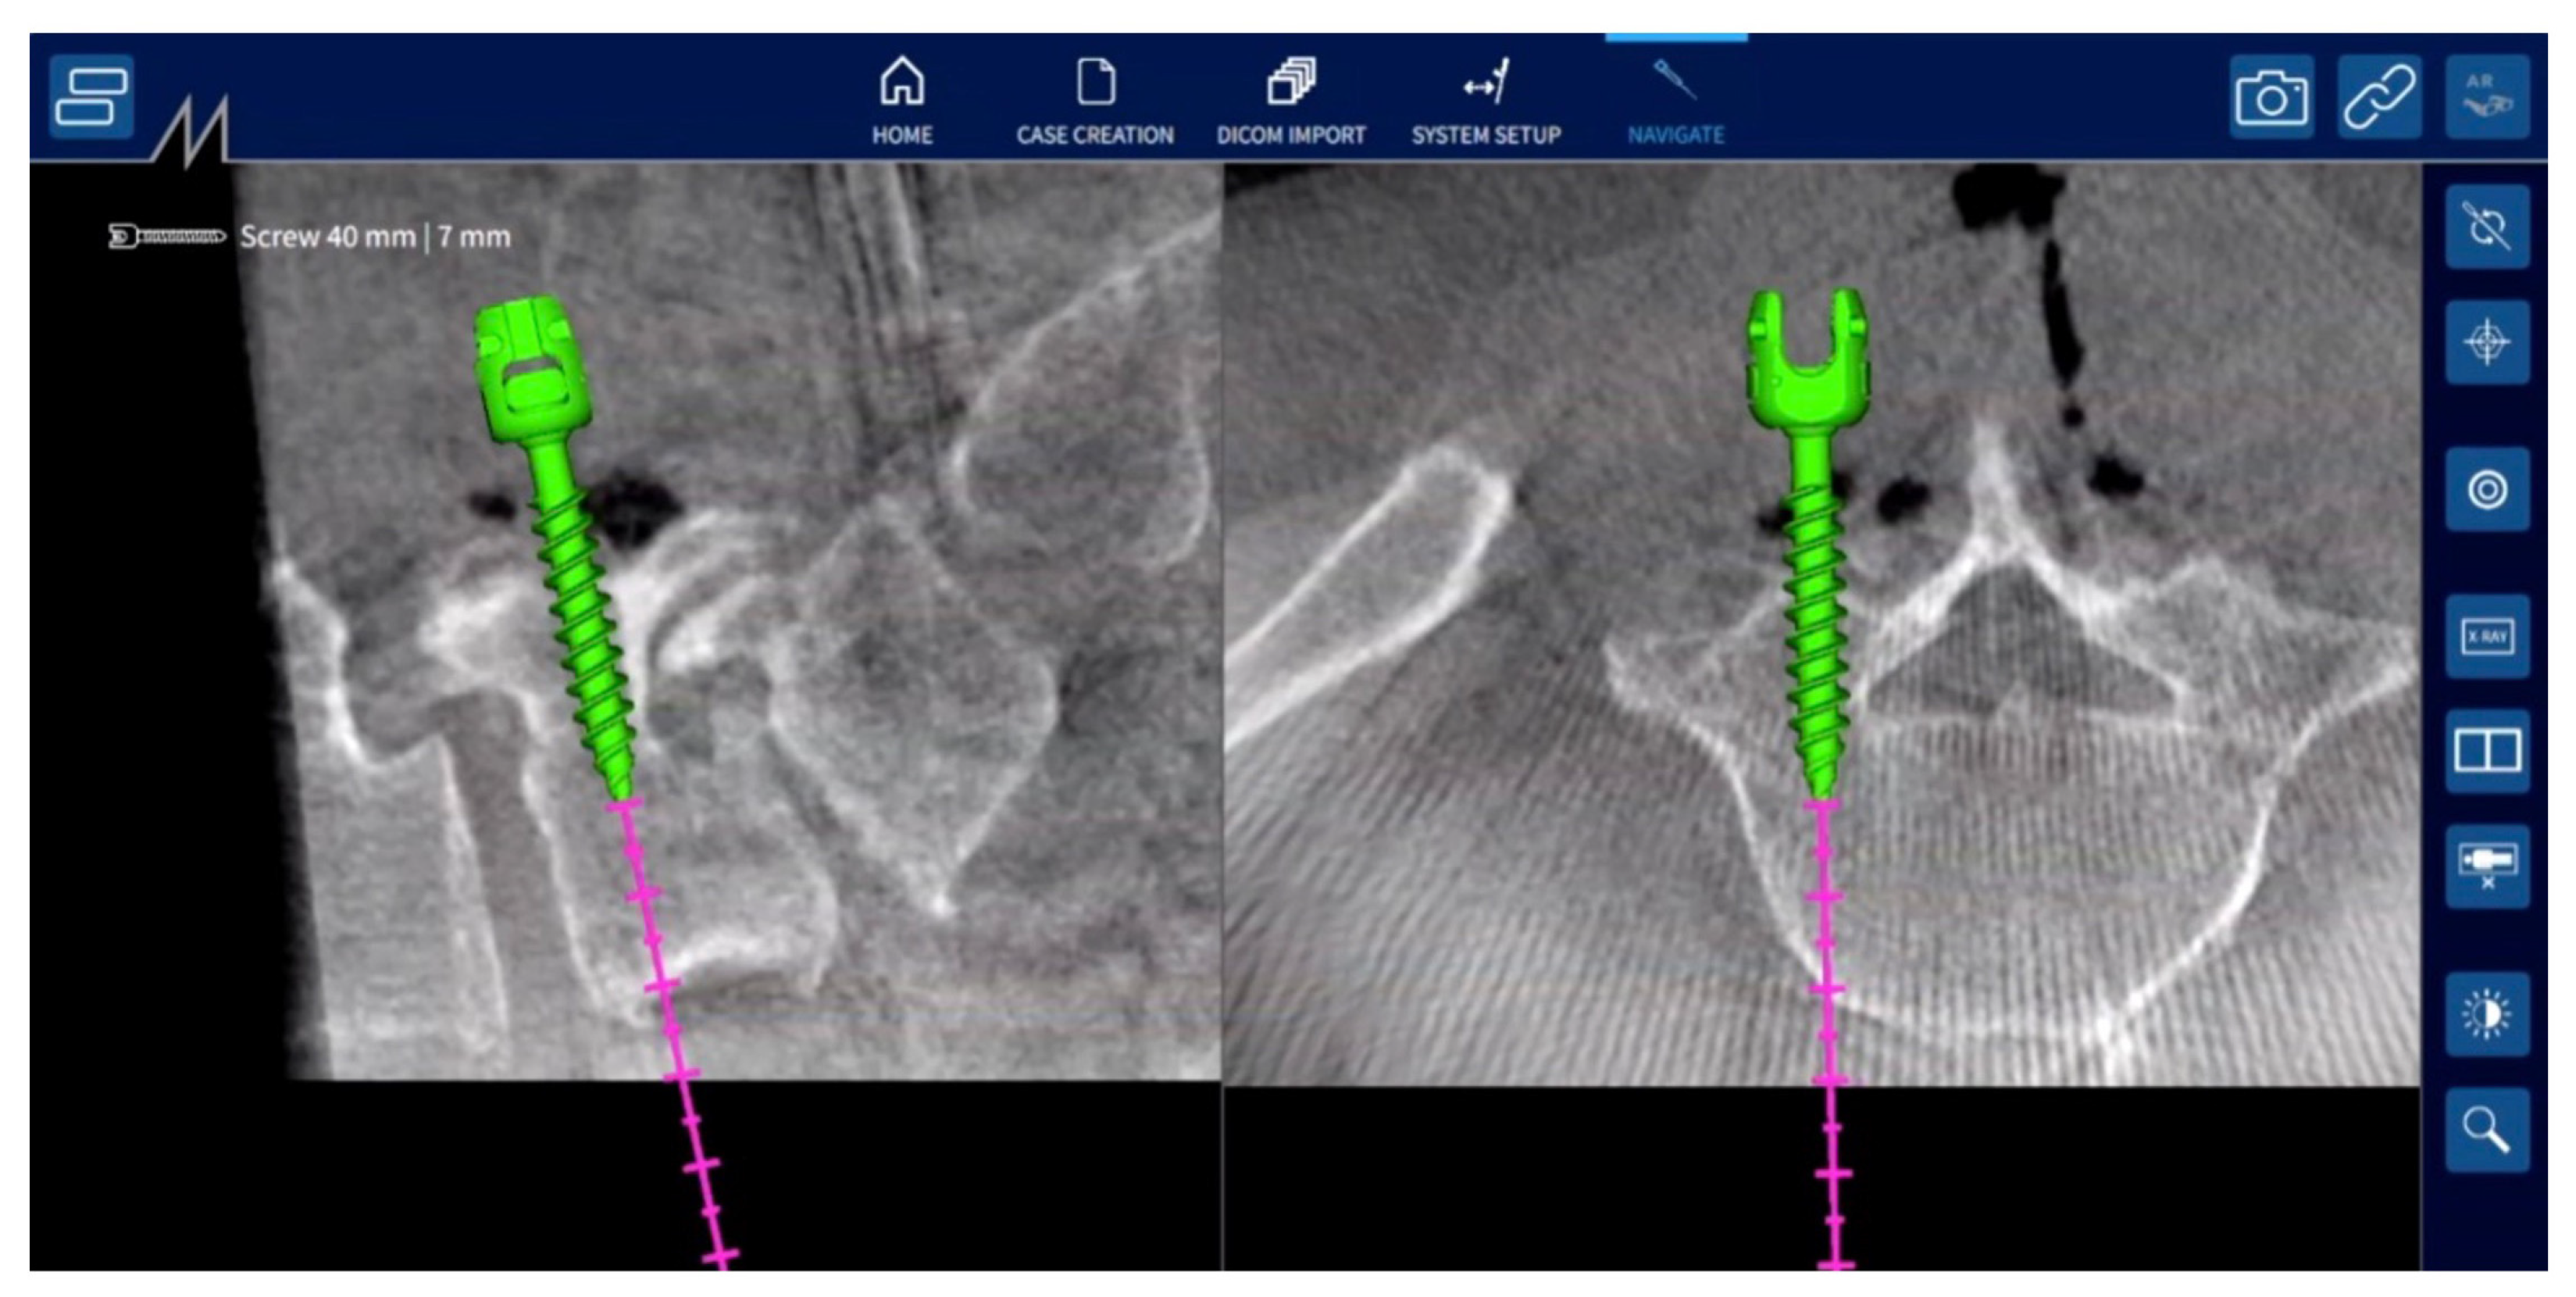

2.2. Navigation System

4. Illustrative Cases